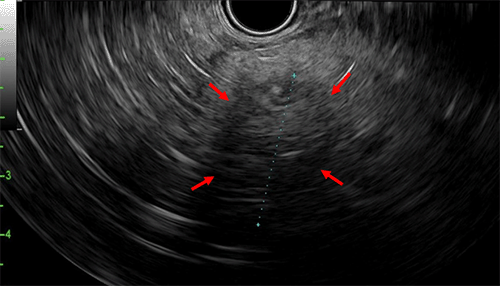

EUS revealed a 2.6 cm hypoechoic, irregular mass in the tail of the pancreas without involvement of adjacent organs (Figure 2). Fine needle aspiration (FNA) revealed ductal epithelial cells with atypia, fragments of stroma with atrophic ductal epithelium, and fat necrosis suggestive of chronic pancreatitis.

Figure 2. Endoscopic Ultrasound of Tail of Pancreas. Published with Permission

Red arrows show irregular hypoechoic lesion measuring 2.6 cm.